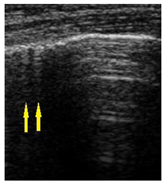

| LUS Score | 0 Points | 1 Point | 2 Points | 3 Points |

| Image | ![]() | ![]() | ![]() | ![]() |

| Description of image | Normal or physiological pattern displaying A-lines (right part), along with two sparse B-lines (yellow arrows) per intercostal space | Three sparse B-lines (yellow arrows) per intercostal space, accompanied by pleural abnormalities, such as irregularities or thickening (orange circle) | Small peripheral consolidations smaller than 1 cm (red dotted area), a small area with ‘white-lung’ appearance, adjacent coalescent or merging B-lines | Substantial peripheral consolidations (marked with red) wider than 1 cm with the presence of air bronchograms (hyperechoic areas inside); the image is from an infant with bacterial pneumonia not included in this study |